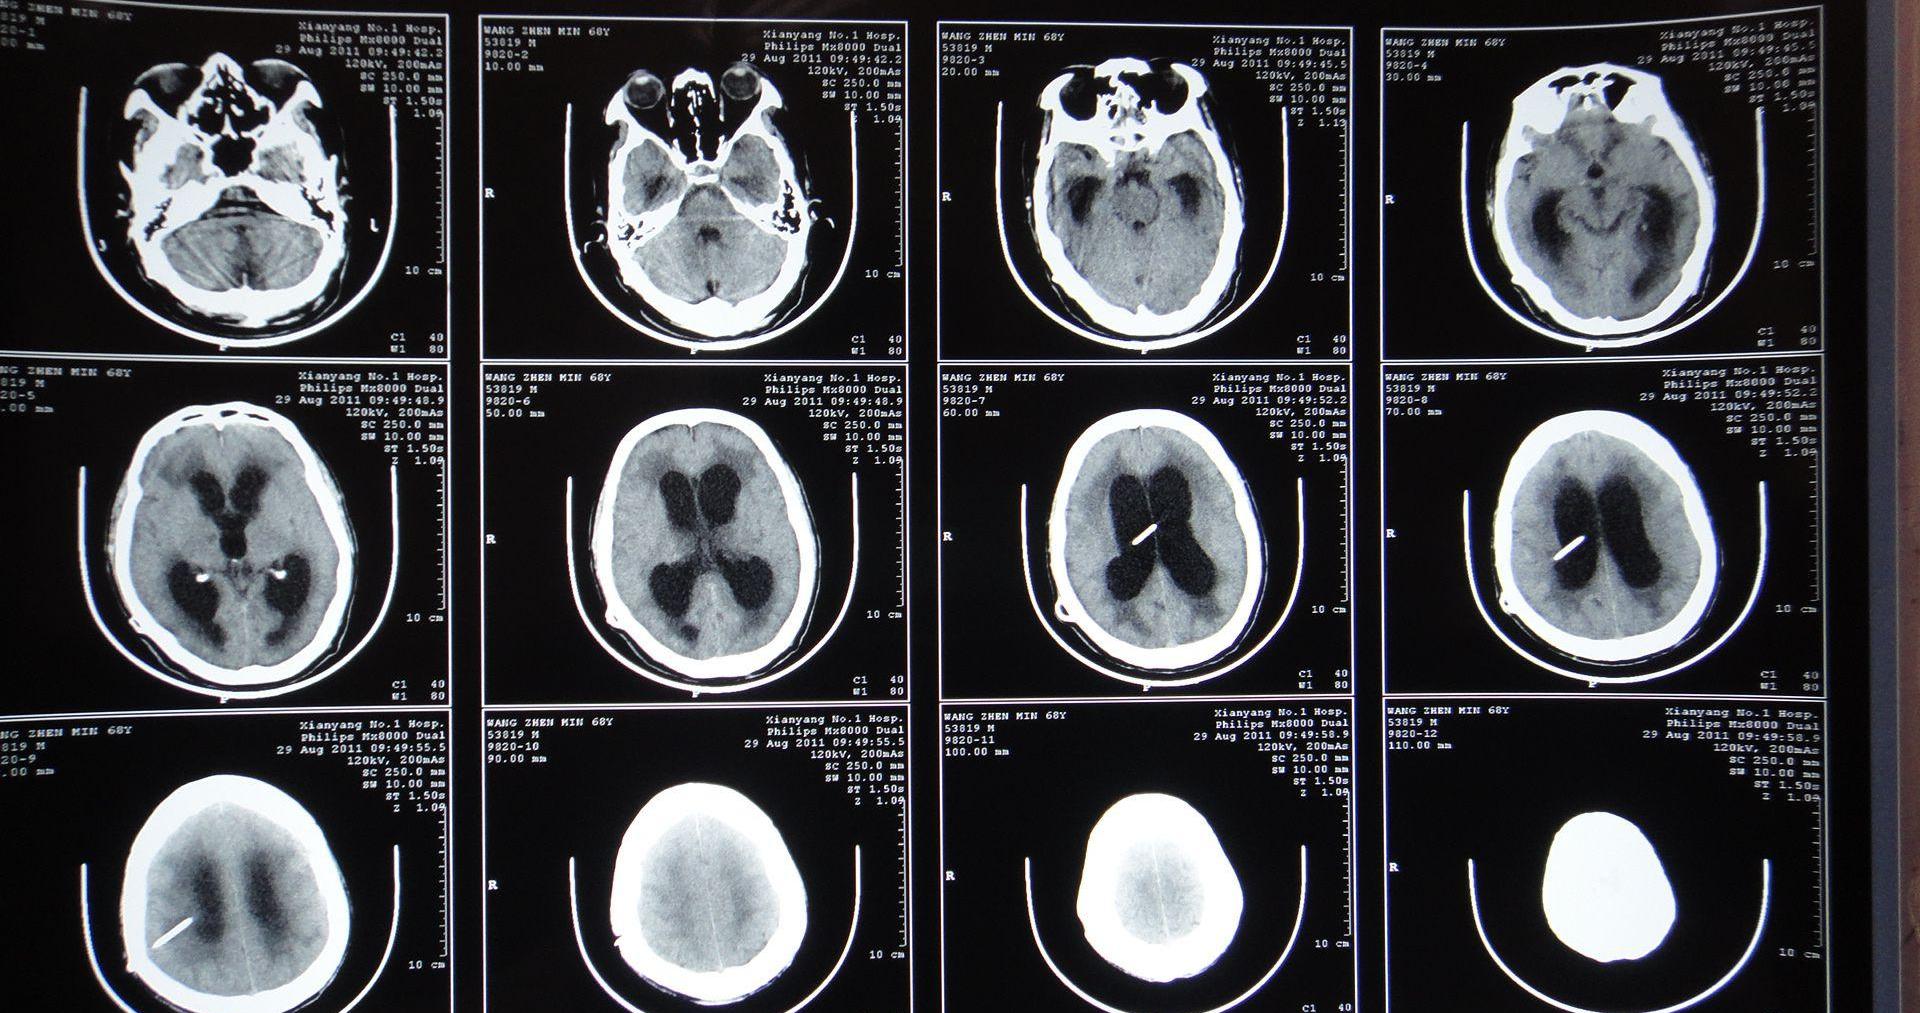

2、CT、MRI扫描检查

显示有脊柱裂,脊髓和神经畸形,局部粘连。